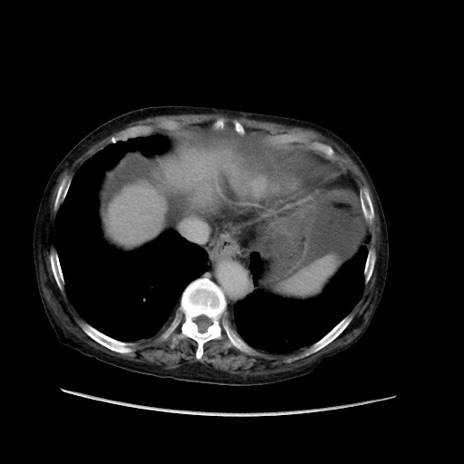

症例31(横断像)

【症例】80歳代 女性

【主訴】腹部膨満感

【現病歴】他院にて肝硬変にてフォロー中。1週間前から便秘、腹部膨満感、臍部腫瘤あり受診となる。

【既往歴】肝硬変

【身体所見】腹部膨隆あり、皮膚変化なし、疼痛なし。

【データ】WBC 4600、CRP 0.25